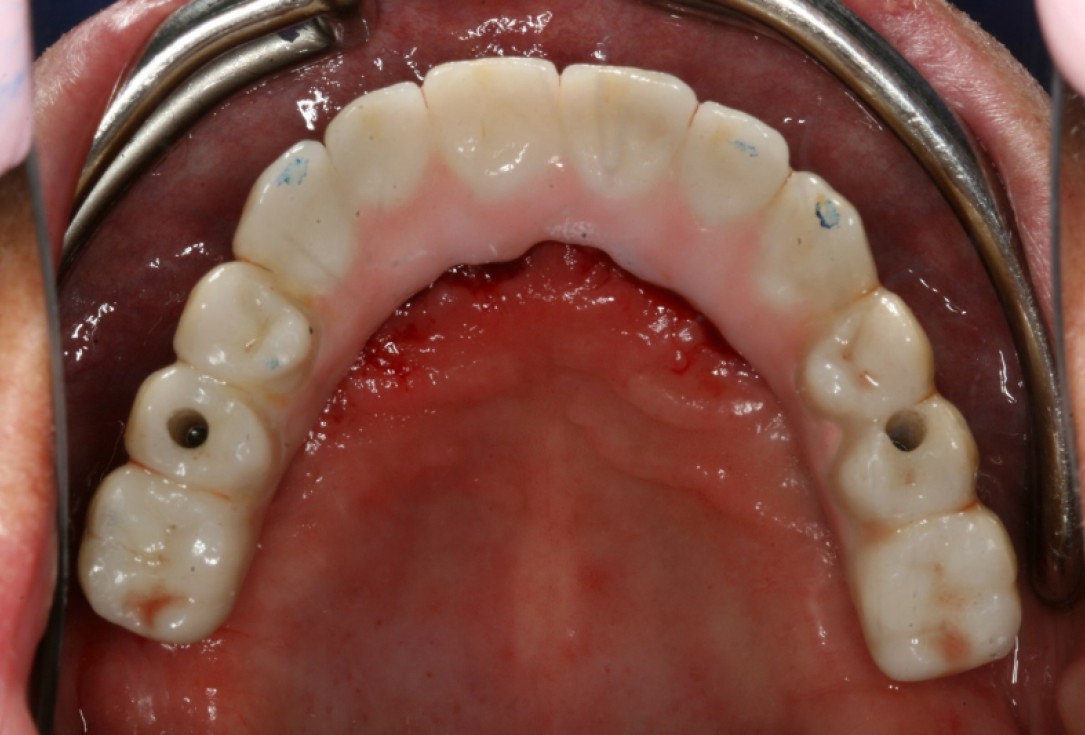

10/10 - Inserted bridge with terminally screwed and anteriorly cemented implantsCircular bone splitting with maxresorb® & collprotect® membrane - PD Dr. J. Neugebauer